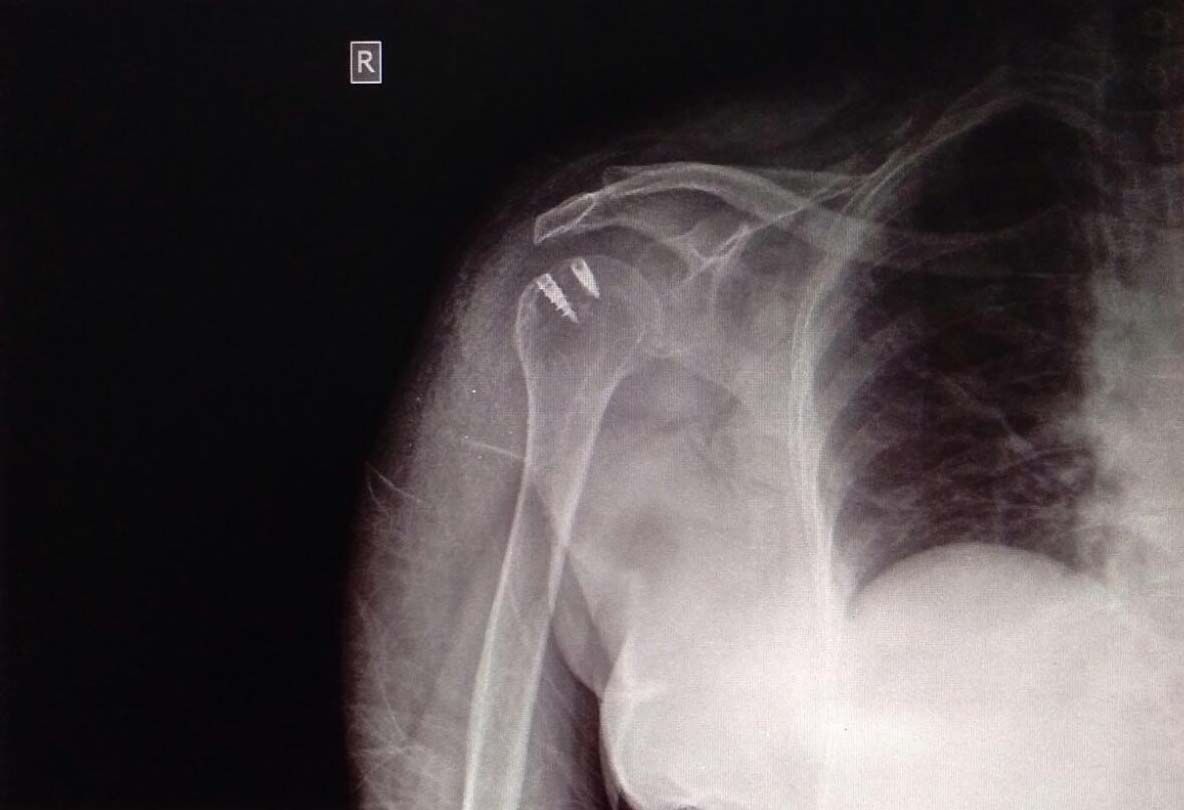

Fracture and Dislocation